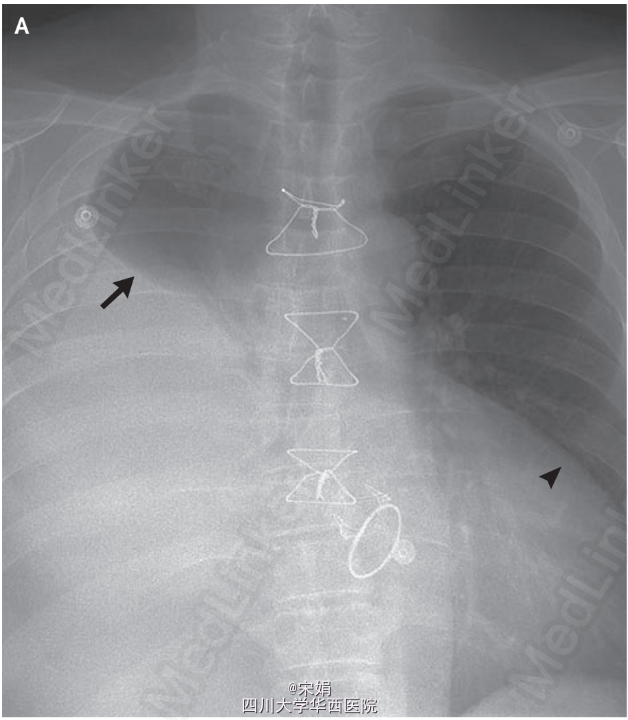

入院时胸片(图A)显示右侧大量胸腔积液(箭号)伴心影增大(箭头)。CT证实存在胸腔积液以及中等量心包积液。